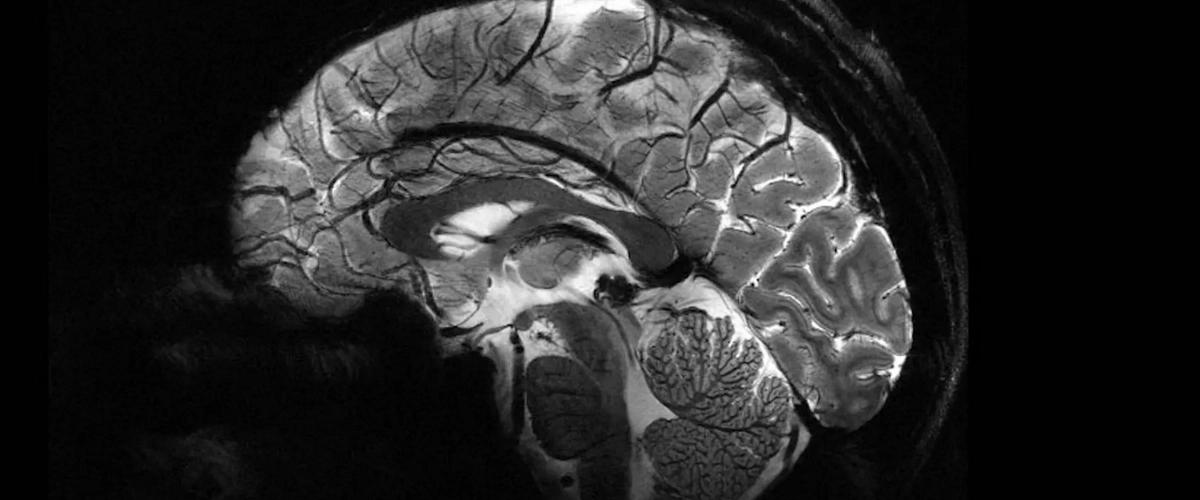

Основное преимущество столь большой мощности магнитов заключается в том, что можно быстро получить изображения мозга в сверхвысоком разрешении. Всего за 4 минуты Iseult может получить сканы мозга размером до 0,2 мм по горизонтали, в виде «срезов» толщиной всего 1 мм. Этот объем эквивалентен нескольким тысячам нейронов.

Чтобы обычные аппараты МРТ могли делать изображения в таком же разрешении, пациентам необходимо лежать совершенно неподвижно более 2 часов — малейшее движение может испортить снимок. По понятным причинам это просто неосуществимо.

Несколько лет назад Iseult тестировали на тыквах, а теперь им впервые просканировали мозг 20 здоровых добровольцев. Настолько качественные снимки позволяют увидеть, как протекают процессы, которые лежат в основе человеческого сознания. Аппарат поможет нейробиологам сделать множество открытий в области работы мышления и памяти.